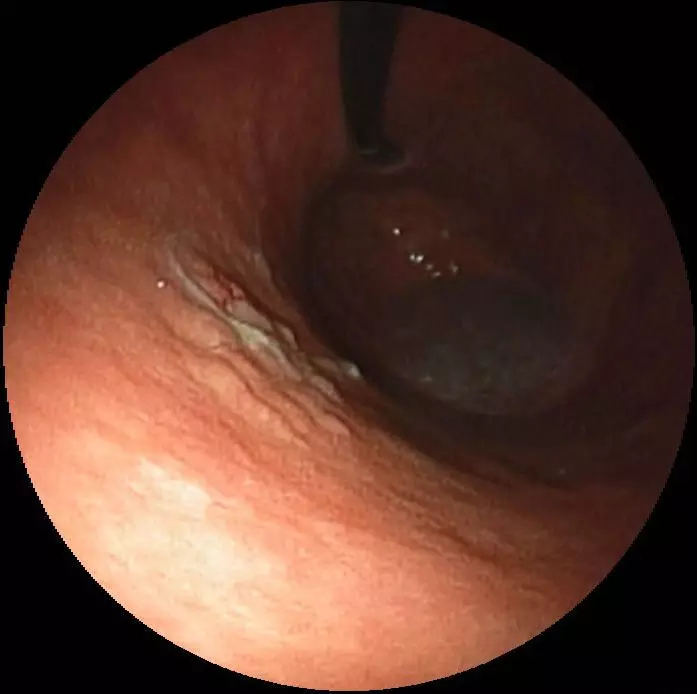

Image - Early gastric cancer in the body of the stomach

Public Domain Source by Med_Chaos [Public domain]